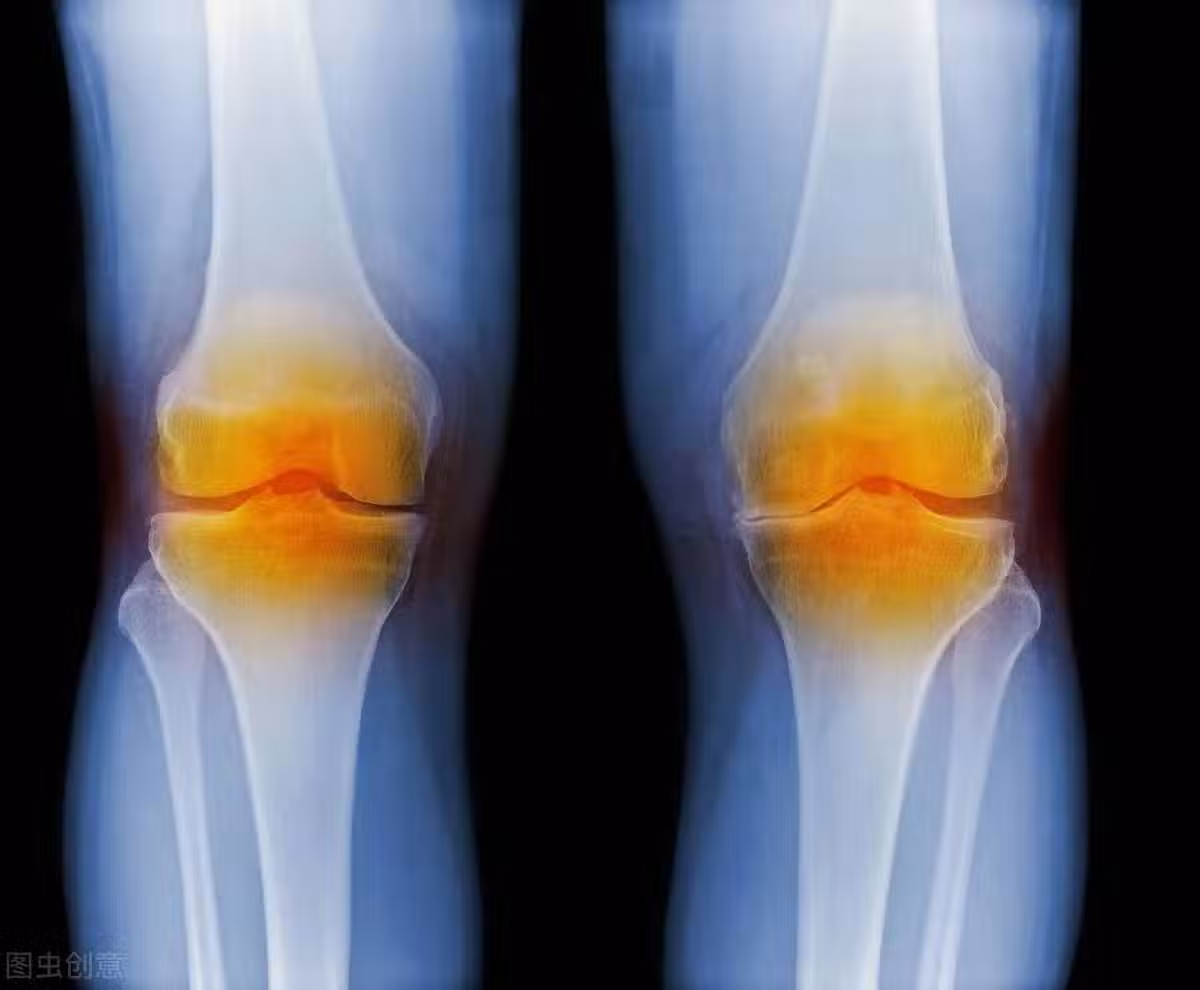

骨科主任:牢記2個方法,膝蓋不疼了,積液消失了,滑膜炎也好了

我們人就是這樣,對於很多慢性疾病,從來不會在意,非要等到嚴重的必須去醫院菜後悔莫及,然而這時候並沒有什麼用,只能接受來自手術或者藥物的「洗禮」,滑膜炎也是如此,前期膝蓋出現疼痛,很多人並沒有在意,不知道調理,晚期的時候,行走困難,甚至出現跛腳,嚴重的導致癱瘓。所以,看到這篇文章的你,一定要有所警惕,不僅對自己,還有家人,如果出現下面這種情形,一定要及時治療。